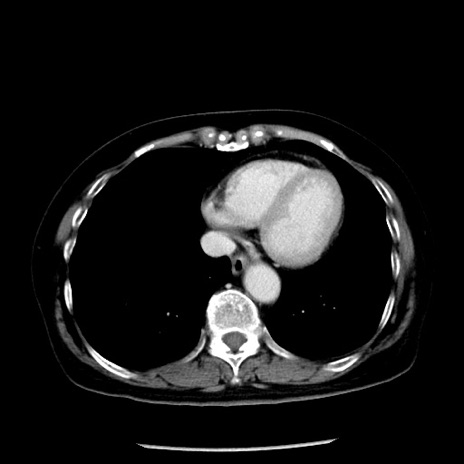

症例13(横断像)

【症例】70歳代女性

【主訴】腹痛、嘔吐

【現病歴】15時間程前(昨晩)より腹痛あり。今朝になっても症状の改善なく、嘔吐あり。腹痛も増悪あり、救急外来受診。

【既往歴】子宮癌全摘術後

【身体所見】意識清明、BP 121/72mmHg、P 74bpm、SpO2 100%(RA)、腹部:平坦・軟、腸雑音ほぼ聴取せず。下腹部・心窩部・臍左上に圧痛あり。反跳痛なし。

【データ】WBC 10600、CRP 0.15